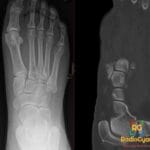

- Radiology Cases: Images with a to-the-point discussion highlighting the specific diagnostic criteria.

- Radiology Case of the Day Collection: Aunt-Minnie Board Cases for Rapid Review.

- Radiology Spotters: 700+ spot / “Aunt-Minnie” cases divided into sets of 10 each!